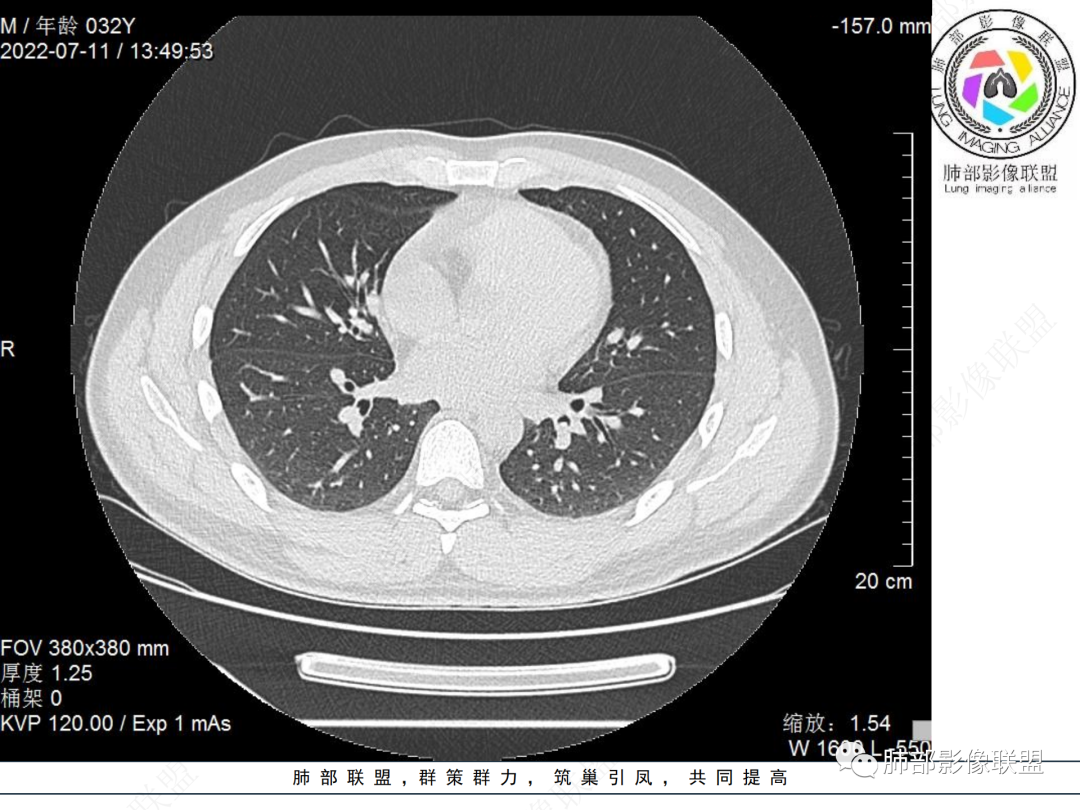

左肺下叶后基底段开口处结节,边缘光滑清楚,没有增强扫描,年轻男性患者痰血三天,考虑1.良性病变:腺瘤、错构瘤、平滑肌瘤

2.恶性:类癌、粘液表皮样癌。

左肺下叶外后基底段气管内见结节状影,边缘部分清晰。考虑错构瘤,待排恶性病变。

左肺下叶气管内外占位病变,咯血病史,考虑类癌,粘表待排。

青年男性,左肺下叶后基底段支气管开口软组织结节,边缘光整,气管镜提示质软,易出血,考虑类癌

左肺下叶后基底段开口处结节,边缘光滑清楚,年轻患者考虑鳞癌或腺样囊腺癌

左肺下叶气道腔内占位,远端无花花草草,疾病谱:鳞,类癌,粘表,腺样囊腺癌,小,无增强,不好判断,临床咯血,选类癌。

大支气管腔内结节,考虑类癌

左肺下叶后基底段开口处结节影,边缘光滑,患者年龄较小,首选类癌

男性,咳血左肺下叶支气管腔内结节影,没有阻塞性炎症,考虑类癌,鳞癌

年轻男性,支气管内结节,首先类癌

左肺下叶后基底段开口处腔内见壁结节,花生米样,宽基底,补充增强及矢状位重建,确定我无向壁外突破浸润生长,另见强化的特点,临床触之易出血,类Ca可能性大。

年轻男性,支气管腔内占位,边缘尚平整,年轻人,首先类癌,鉴别错构

年轻男性,咳血,左肺下叶后基底段支气管腔内结节,边缘光滑,首先考虑青年三件套,类癌大于粘液表皮样癌,支气管镜质软,触之易出血,鉴别血管瘤,平滑肌瘤

左肺下叶后基底段开口部结节,密度较均匀一致,边缘较光整,目测密度偏低,支气管镜示:质软、触之易出血,考虑恶性,类癌。

支气管腔内结节,有蒂与支气管壁连接,考虑良性病变可能性大,支气管错构瘤 血管瘤一类的

左肺下叶后基底段支气管腔内结节,有蒂,容易出血,先考虑良性病变,肉芽组织型血管瘤,与类癌鉴别。

青年男性,左肺下叶后基底段支气管开口软组织结节,边缘光整,气管镜提示质软,易出血,考虑恶性类癌

左肺下叶后基底段开口处结节影,边缘光整,年轻患者,伴咯血,考虑鳞癌,类癌不能排除